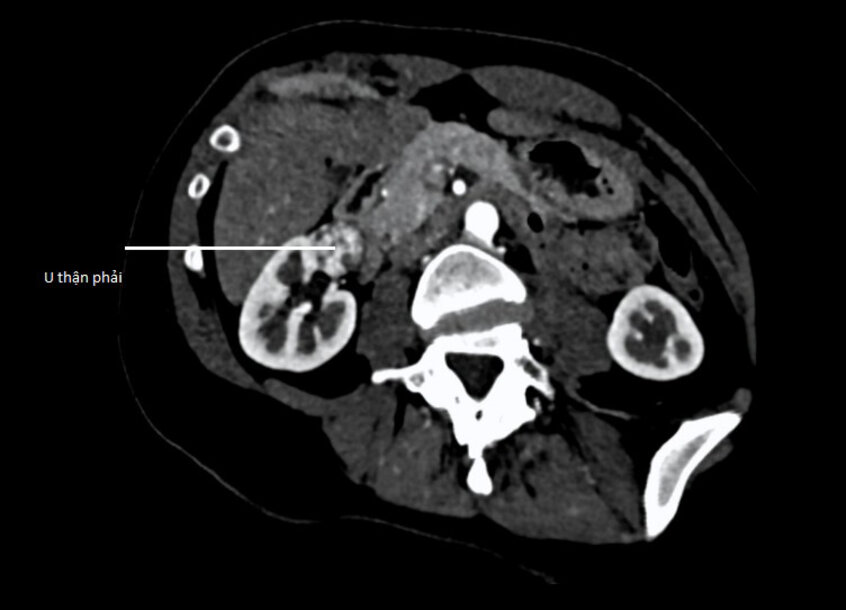

Tái khám theo dõi sau mổ u tuyến thượng thận, bác sĩ phát hiện chị An có tổn thương ở thận phải qua siêu âm, kích thước u 12×18 mm. 3 tháng sau u tăng thêm khoảng 5 mm. Người bệnh được chụp cắt lớp vi tính cắt lớp (CT Scan) vùng bụng, ghi nhận một khối u ở mặt trước thận phải nghi ngờ ung thư. Hình ảnh tương đối điển hình, u có đường kính khoảng 22 mm, tăng quang không đồng nhất, giới hạn rõ, gần rốn thận.

“Người bệnh cần nhanh chóng loại bỏ khối u nghi ung thư. Tuy nhiên trường hợp này u nằm ở vị trí khó tiếp cận, ở mặt trước và 1/3 giữa gần rốn thận, sát động mạch cực dưới của thận nên không thể thực hiện được bằng kỹ thuật đốt bằng sóng cao tần (RFA). Thay vào đó, cần can thiệp bằng phẫu thuật cắt bỏ khối u, bảo tồn thận”, bác sĩ Cương nói.